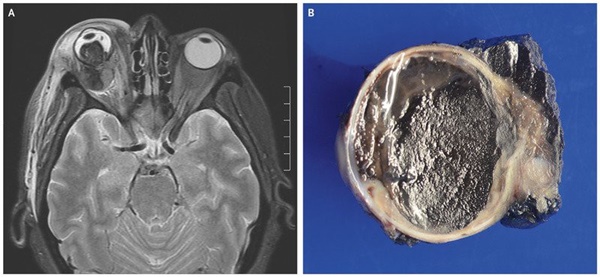

Bản báo cáo cho biết mắt phải của người này đã không còn nhìn được trong vài năm gần đây nhưng không đề cập đến quá trình ấy diễn ra như thế nào. Chỉ biết rằng con mắt ấy đã bị hư hại nặng, sắc tố trong tròng mắt lan ra khắp nhãn cầu theo như bức hình dưới đây.

Con mắt của người phụ nữ sau khi mổ ra.